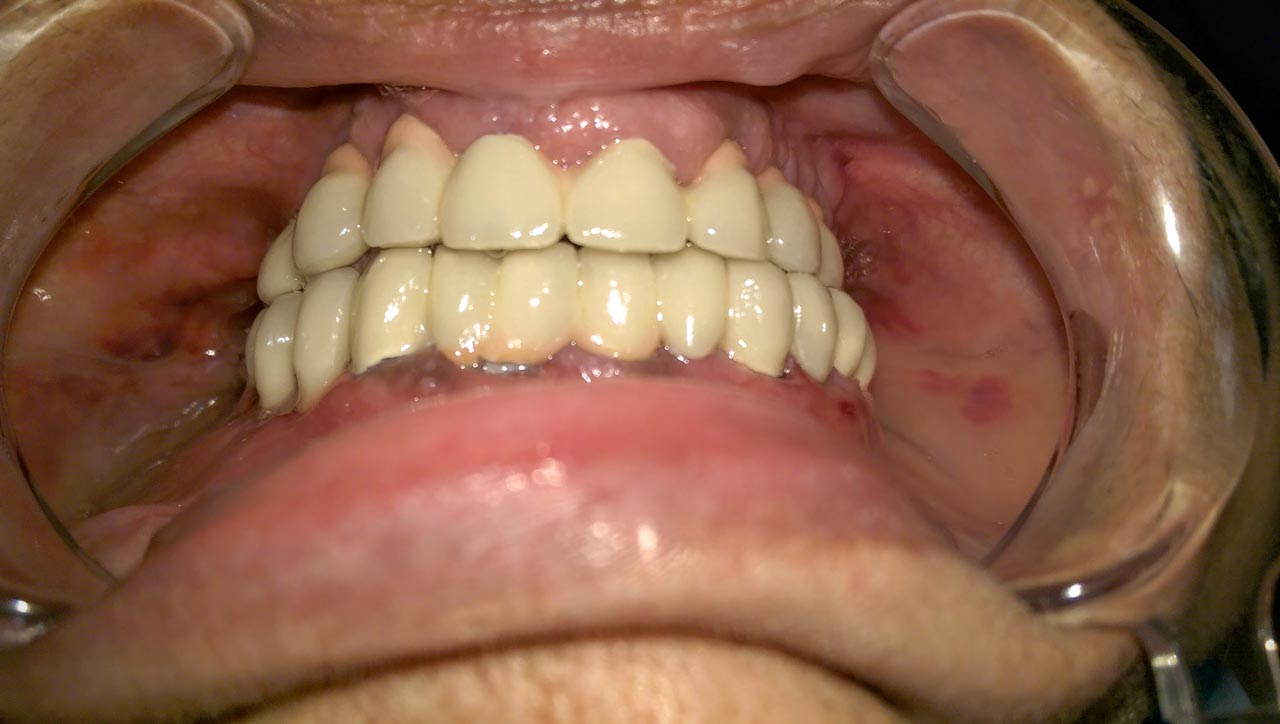

Elhanyagolt fogsor cseréje 2 nap alatt

2 nap alatt varázsoltuk ezt a szép esztétikus alsó, felső körhídat implantátumokkal megtámasztva a korábban elhanyagolt szájba. Az 1. nap 26 fogat távolítottunk el, mert annyira rossz állapotban voltak, és rögtön azonnal terhelhető IHDE svájci implantátumokat raktunk be, fentre 8, lentre 6 darabot. A sebeket összevarrtuk és intraorális szkennerrel digitális lenyomatot vettünk. 2 nap múlva pedig beragasztottuk a kész PMMA műanyag körhidakat. Dr. Kelemen Péter és a Symbion Fogtechnika munkája.